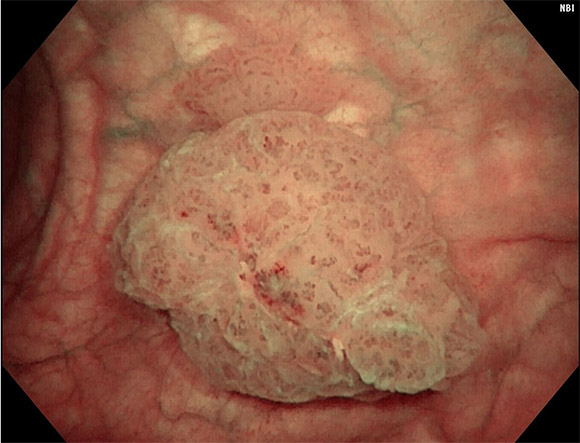

- 방광경 검사 : 방광경을 이용하여 방광 내부를 직접 관찰하고 종양의 유무를 확인합니다. 이 과정에서 조직을 채취해 생검도 진행할 수 있습니다.